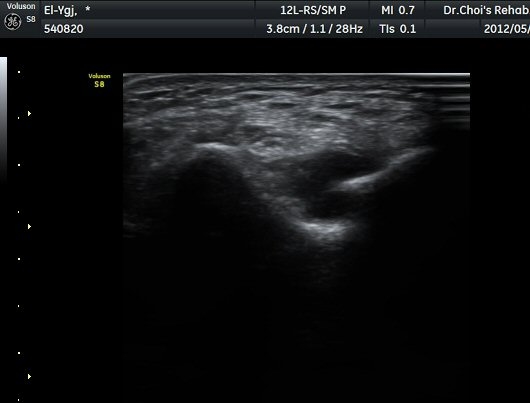

ÆÈ²ÞÄ¡ ¿ÜÃø Á¾´Ü¸é°Ë»ç¿¡¼­ ¼ÒµÎ ¾ÕÂÊ¿¡ ¼ö¾×Àú·ù°¡ °üÂûµÈ´Ù(±×¸² 1).